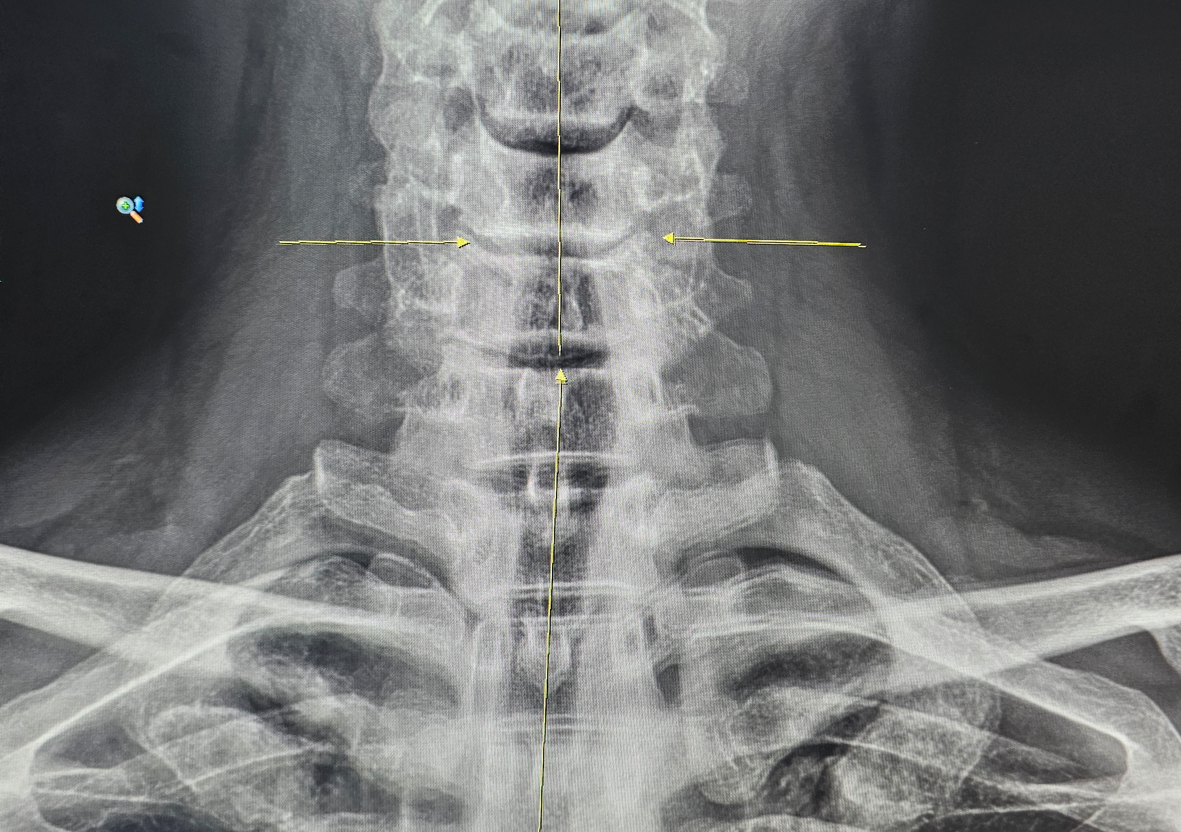

엑스레이도 찍고, 상세한 의사선생님의 진단도 받았다. 5번 목디스크가 많이 닳아 없어졌고, 6번 뼈와 간격 도 많이 좁혀 졌단다. 목뼈가 심각한 것은 아니지만 기울어 있어서 근육과 신경에 무리를 주고 있다고 했다.

정말 다행이게도 아직 디스크는 아니란다. 경직된 승모근을 자주 이완시켜야 하는데, 오히려 계속 피로감을 주고 경직시켜 일어난 일이라고 한다.